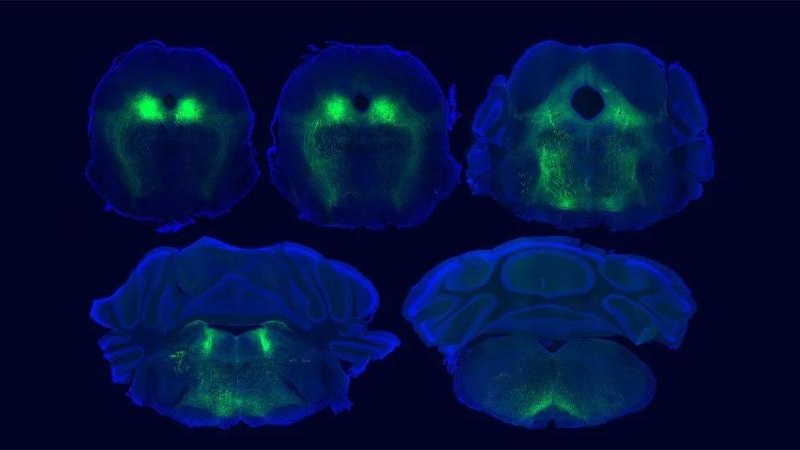

Badacze wykazali, że istotną rolę odgrywają połączenia między korą mózgową, pniem mózgu i rdzeniem kręgowym. Kluczowe okazały się również naturalne opioidy produkowane przez sam organizm, czyli endorfiny. To właśnie one uruchamiają przeciwbólowe działanie placebo w określonych rejonach mózgu.

Badacze sięgnęli po nowoczesne narzędzia, które pozwoliły im śledzić aktywność naturalnych opioidów i sprawdzić, gdzie dokładnie działają. W jednym z kluczowych obszarów mózgu udało się potwierdzić, że zarówno ulga po morfinie, jak i ulga wywołana placebo korzystają z podobnego mechanizmu sygnalizacji opioidowej.